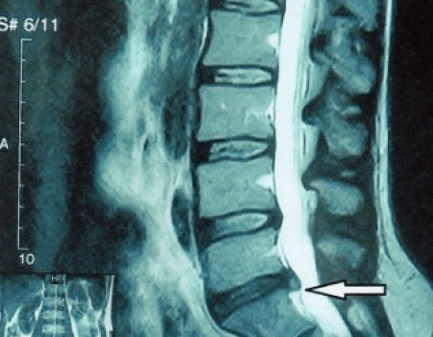

Since the discs themselves can only be seen by CT or MRI, magnetic resonance imaging and X-ray computed tomography are indicated to clarify the internal structure of the cartilage and formations such as protrusions and hernias.Therefore, with the help of these methods, an accurate diagnosis is made, and the result of tomography constitutes an indication, and even a topical guide, for surgical treatment of hernia in the neurosurgery department.

- if you have a hernia, then you need to dynamically monitor it, do regular MRI scans, avoid increasing its size or carry out modern minimally invasive surgical treatment, since without exception, all conservative methods of treating exacerbation of osteochondrosis leave the hernia in place and eliminate only temporary symptoms: inflammation, pain, shooting and muscle spasms.

Surgical treatment or conservative measures?

It is advisable that every patient, after the progression of symptoms, in the presence of complications, undergoes an MRI and consults a neurosurgeon.Modern minimally invasive interventions allow you to safely remove fairly large hernias, without prolonged hospitalization, without being forced to lie down for several days, without compromising the quality of life, since they are performed using modern videoendoscopy, radiofrequency, laser technology or using cold plasma.You can evaporate some of the core and lower your blood pressure, reducing the risk of hernia.And you can eliminate the defect radically, that is, eliminating it completely.